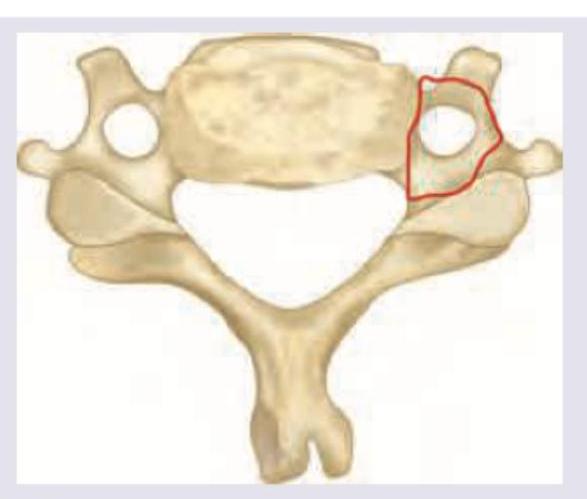

Which structure passes through the area marked in red? (AIIMS May 2018)

Explanation: ***Vertebral artery*** - The image displays a cervical vertebra, and the red-marked area highlights the **foramen transversarium** (or transverse foramen). This foramen is a defining feature of cervical vertebrae. - The **vertebral artery** ascends through these foramina in cervical vertebrae C1-C6, providing blood supply to the brain. *Anterior inferior cerebellar artery* - The **anterior inferior cerebellar artery (AICA)** is a branch of the basilar artery and supplies parts of the cerebellum and brainstem. - It is an **intracranial vessel** and does not pass through the foramina transversaria of the cervical vertebrae. *Transverse ligament* - The **transverse ligament of the atlas** is a crucial ligament that holds the dens of the axis against the anterior arch of the atlas. - It is located **within the vertebral canal**, posterior to the dens, not within the foramen transversarium of the transverse process. *Apical ligament* - The **apical ligament** connects the apex of the dens (odontoid process) of C2 (axis) to the anterior margin of the foramen magnum. - Like the transverse ligament, it is an **intracranial ligament** associated with the craniocervical junction, not a structure passing through the foramen transversarium.